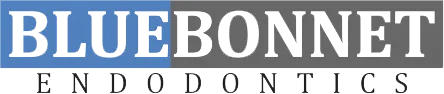

Before

After

Patient is a 62 year old female. She was seen for retreatment of teeth 24, 25, 26 on 5-3-21. We did see her for re-evaluation 4 months post treatment area is not healing as expected a CBCT was taken for comparison. Dr. Malavia is recommending Apicoetomy surgery. Surgery was completed 10-13-21, Final x-ray taken 5-19-2022.